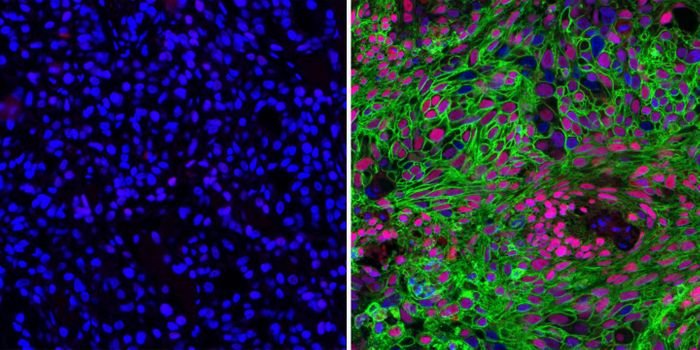

NOV 29, 2023CancerThe CAR-T Revolution: Developing T Cells into Cancer Assassins Cancer has long been a formidable foe, but recent ...

MAY 22, 2017ImmunologyThree new approaches to anticancer drug therapy were combined in a recent study to simultaneously maximize destruction o ...